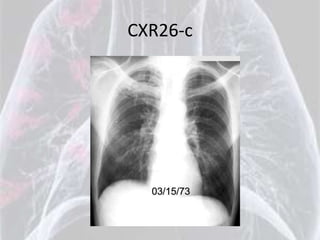

CXR26-c

Diagnosis for CXR26 is: Ankylosing Spondylitis

Bamboo spine